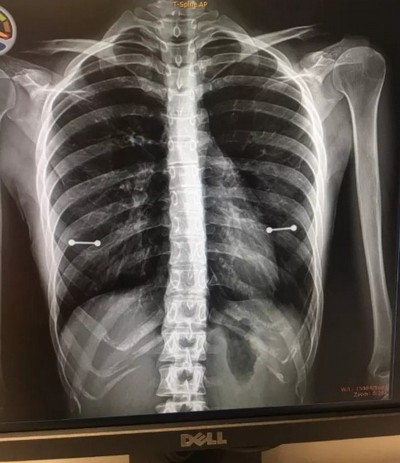

Дело в том, что Сидни страдает от сирингомиелии – это заболевание, вызывающее в спинном мозге образование полостей. В связи с этим девушке регулярно приходилось проходить рентгенологическое обследование.

Вероятно, Аллен не знала или же забыла о том, что любые металлические предметы хорошо видны на готовых снимках. Иначе вряд ли бы она взяла с собой мать на очередное обследование в октябре.

Именно в этот день секрет сосков Сидни Аллен был раскрыт. Рентгеновский снимок высветился на компьютерном экране, и на нем отчетливо просматривались металлические штанги в районе груди Сидни. Доктор и сама пациентка, увидев это, начали хохотать.

Мать девушки тоже просто не могла не заметить пирсинг. Она долго смотрела на экран и, наконец, сказала:

«Мы обсудим это позже».

Опасения американки были напрасны – родительница не стала сильно ругать ее за прокол, ведь его все-таки не видно под одеждой. Сама же девушка решила поделиться своей забавной историей в Твиттере. Меньше чем за неделю ее пост набрал более 33 тысяч ретвитов. Судя по комментариям, Сидни Аллен – не единственная, кто точно так же прокололся перед родителями.